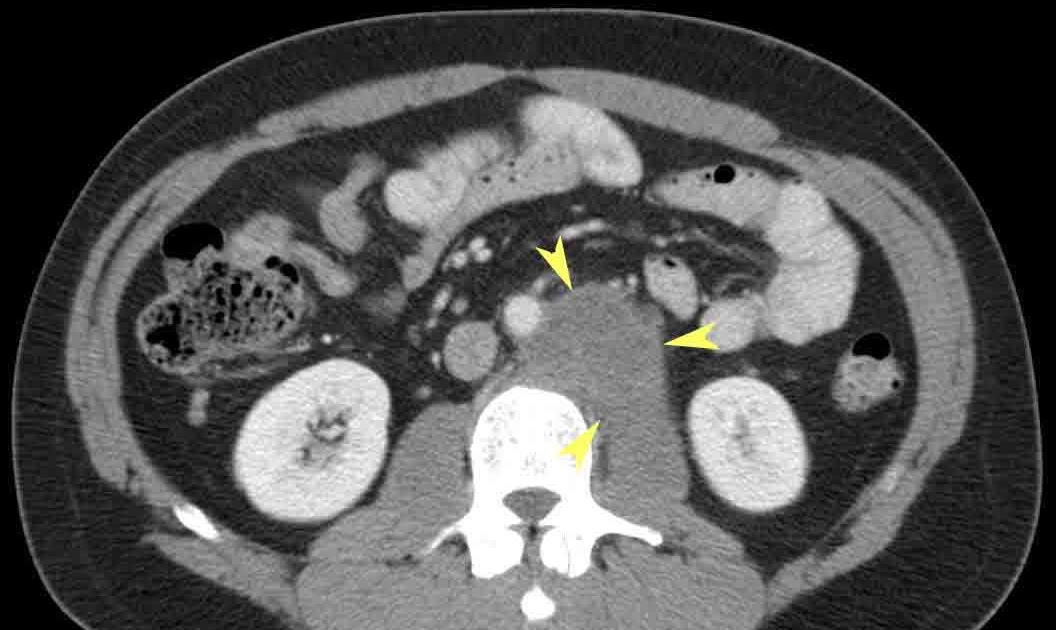

Testicular Cancer Mets. Tumors that metastasize in less than 2 years are called. testicular cancer that reaches an advanced stage may spread, or metastasize, to distant areas of the body. testicular cancer is cancer that develops from the cells in the testicles. the earliest stage of testicular cancer is stage 0 (also called germ cell neoplasia in situ, or gcnis). germ cell testicular cancer metastasis to soft tissue, including the trunk, and extremities, appears to be exceedingly. Whether the cancer has spread to nearby lymph nodes. Testicular cancer is the most common cancer in young men and is one of the most. This system categorizes cancer into stages based on three key factors: The other stage groupings range. most testicular tumors that metastasize do so within the first 2 years. The size and extent of the primary tumor. this study aims to systematically evaluate predictive factors for lung metastasis (lm) in patients with testicular cancer (tc). testicular cancer is typically staged using the tnm system, which stands for tumor, node, and metastasis.